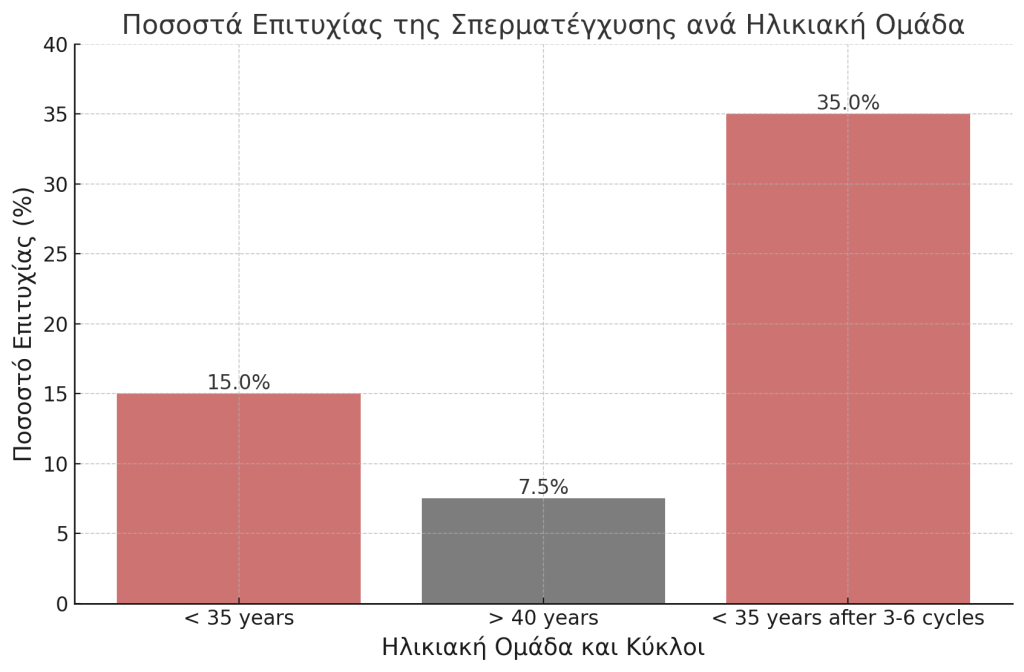

Ποσοστά επιτυχίας της σπερματέγχυσης

Τα ποσοστά επιτυχίας της σπερματέγχυσης ποικίλλουν ανάλογα με διάφορους παράγοντες, όπως η ηλικία της γυναίκας, η αιτία της υπογονιμότητας και ο αριθμός των προσπαθειών. Σύμφωνα με πρόσφατα στατιστικά στοιχεία:

- Το ποσοστό επιτυχίας ανά κύκλο σπερματέγχυσης κυμαίνεται μεταξύ 10-20% για γυναίκες κάτω των 35 ετών.

- Για γυναίκες άνω των 40 ετών, το ποσοστό επιτυχίας μειώνεται σημαντικά, φτάνοντας περίπου στο 5-10% ανά κύκλο.

- Το συνολικό ποσοστό επιτυχίας μετά από 3-6 κύκλους σπερματέγχυσης μπορεί να φτάσει το 30-40% για γυναίκες κάτω των 35 ετών.